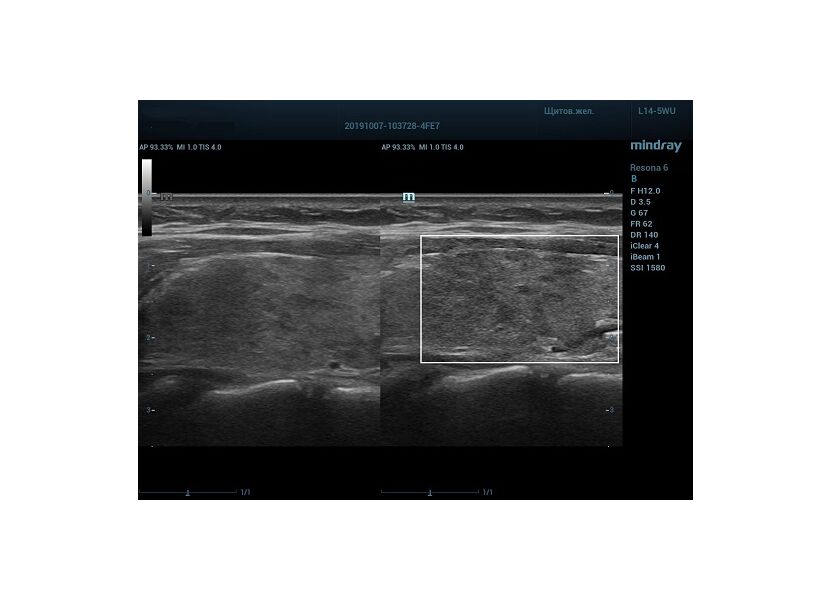

HD Scope позволяет достигать поразительной разрешающей способности выбранной зоны сканирования, при этом улучшая как детализацию, так и контрастность изображения. Помимо пространственного разрешения мы получаем преимущество и по разрешению во времени. Прибор получает огромное количество нативных изображений практически одновременно, и при сборе итоговой картины не происходит смещения объекта под датчиком, а значит и нет размывания изображения. Все участки раздела фаз, каждый контур образования теперь видны, мы все ближе к идеальной картинке.